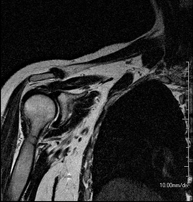

- RM Hombro

Exploración para el estudio de lesiones en tendones, músculos y articulación. Su principal utilidad reside en diagnosticar las lesiones de los tendones del manguito rotador. Tiene una duración aproximada de 20 minutos. No emplea radiación ionizante. - RM Brazo